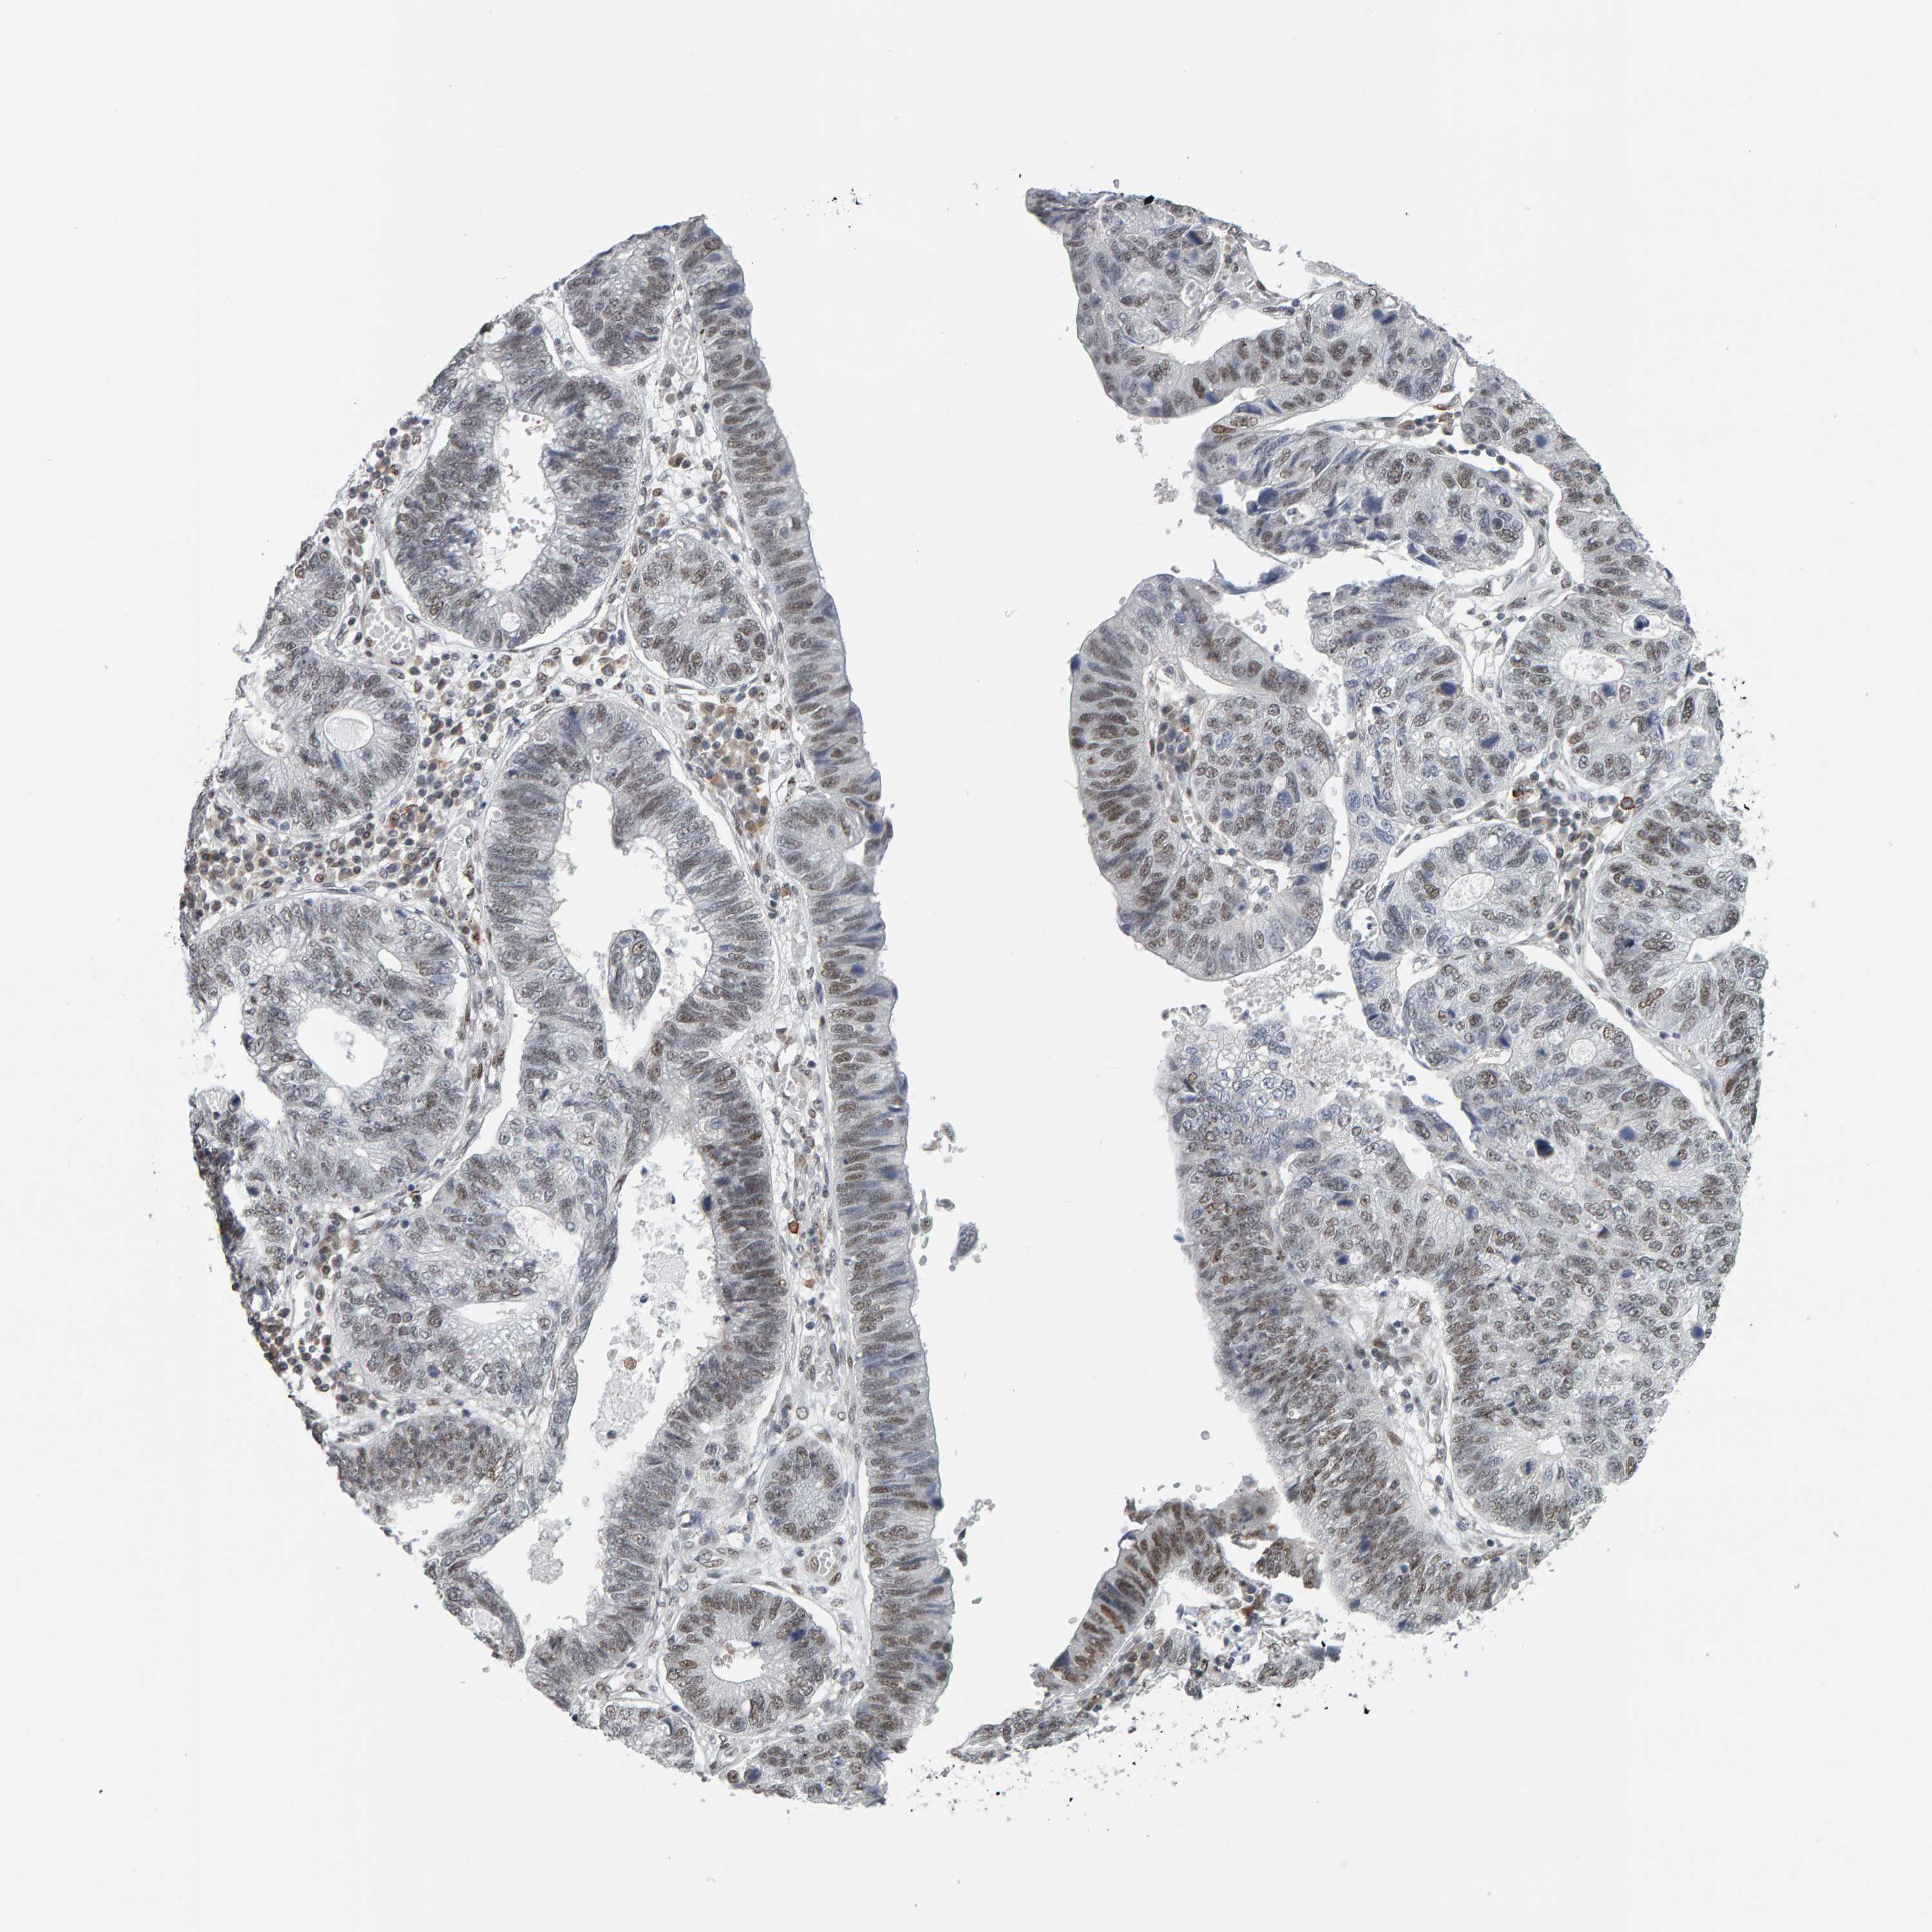

STOMACH CANCER - Protein expressioni

A mouse-over function shows sample information and annotation data. Click on an image to view it in a full screen mode. Samples can be filtered based on level of antibody staining by selecting one or several of the following categories: high, medium, low and not detected. The assay and annotation is described here.

Antibody stainingi

Antibody staining in the annotated cell types in the current human tissue is reported as not detected, low, medium, or high, based on conventional immunohistochemistry profiling in selected tissues. This score is based on the combination of the staining intensity and fraction of stained cells.

Each image is clickable and will lead to virtual microscopy that enables deeper exploration of all samples and also displays staining intensity scores, fraction scores and subcellular localization as well as patient and tissue information for each sample.

Antibody HPA016578

Antibody HPA023505

Staining

High

Medium

Low

Not detected

Intensity

Strong

Moderate

Weak

Negative

Quantity

>75%

75%-25%

<25%

None

Location

Nuclear

Cytoplasmic/membranous

Cytoplasmic/membranous,nuclear

Adenocarcinoma, NOS